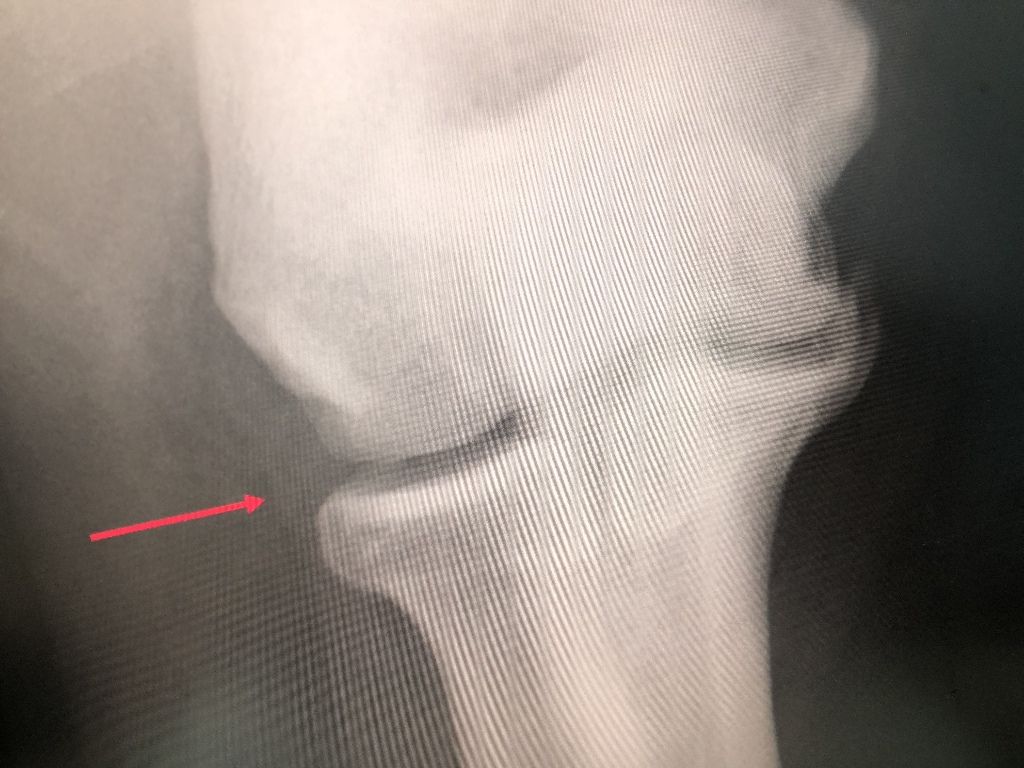

地元の力士が

時々治療にきます、

肘の相談、とてつもない張り手などで、

両肘が変形してます。